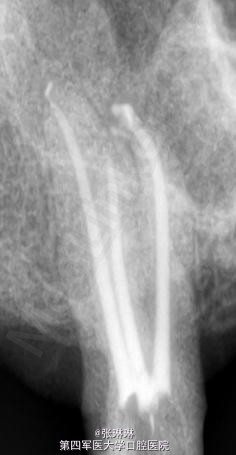

根据龋坏程度、患者的症状、修复需要,且对收费及牙髓处理均征得同意后第一次行右下4、5,左下4、5、6;第二次行左下2,右下2 ,右上7一次性根管治疗术, 术后见右下4,左下4均有侧支充填,且位置对称,左下6近中根中部有侧支;左下5、左下6远中根管均多个开口。 热牙胶垂直加压后有封闭剂和牙胶超填,但无术后反应。